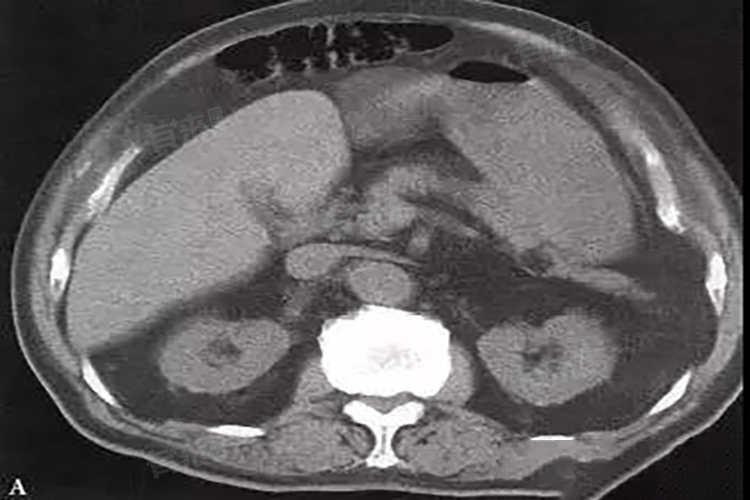

- 对于存在胰腺脂肪浸润的情况,即使癌变风险相对较低,也需要定期进行影像学检查如超声、CT等和相关的血液指标检测如肿瘤标志物。通过定期监测,可以及时发现胰腺的异常变化,做到早期诊断和治疗,提高治疗效果和生存率。